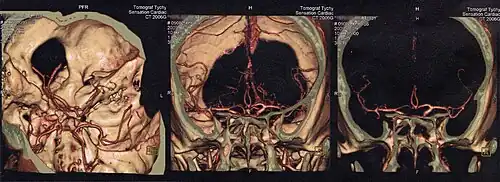

Głowa

Tomografia komputerowa jest obecnie podstawowym badaniem obrazowym pozwalającym na uwidocznienie struktur śródczaszkowych. Powinna być wykonana jak najszybciej w przypadku udaru mózgu w celu zróżnicowania pomiędzy udarem niedokrwiennym i krwotocznym. Pozwala też wykryć obecność guza śródczaszkowego albo krwiaka pourazowego.